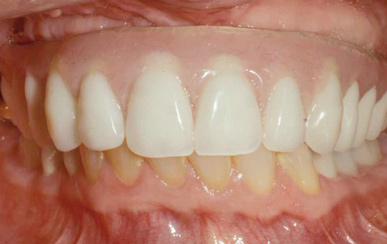

Fig 16. This all-resin interim restoration, which served as a fixed long-term provisional for more than 5 years, is an example of an entry-level option that offers the physiologic benefits of a long-term fixed restoration but with an economic equivalence to a mandibular two-implant overdenture.

Figure 16

As an alternative to the relatively expensive traditional hybrid restoration that the senior population may perceive as unattainable at their age, an immediate-load all-resin provisional may often be a reasonable option as an entry-level prosthesis. This can serve for extended periods or indefinitely, and when made with a sufficient volume of resin and opposing a light occlusion such as a maxillary denture, it can offer the benefit of fixed retention at a significant reduction in expense (Figure 15 and Figure 16). Technology involving a guided approach for placing three implants universally in the same sites with pre-manufactured, one-size-fits-all bar components in the mandible can now allow placement of a final restoration in one day, again at a significantly reduced cost (Figure 17 and Figure 18).24-26 Both of these fixed options—the resin long-term provisional and the three-implant bridge—are economically comparable to the most commonly considered implant prosthesis for elderly patients, the two-implant overdenture. In contrast to the latter, however, both fixed restorations offer significant advantages in bite force, bone preservation, maintenance, and patient satisfaction that are simply unachievable with the removable implant overdenture prosthesis.27-31